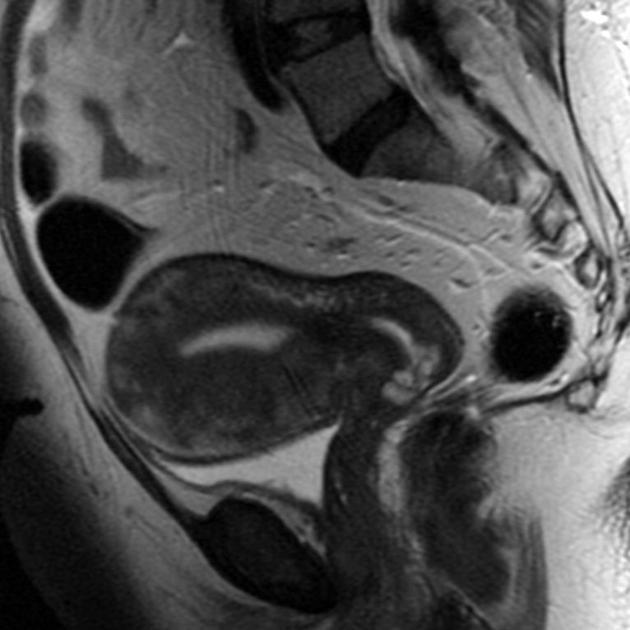

Diagnosis?

Cause?

Adenomyosis.

Focal or diffuse invasion of endometrial tissue into the myometrium. Look for asymmetric thickening of the junctional zone (>12 mm), 50% have small cystic lesions in the myometrium. The endometrium looks normal.

Note- because the basal layer of the endometrium invades the myometrium, it does not show changes with the menstrual cycle.